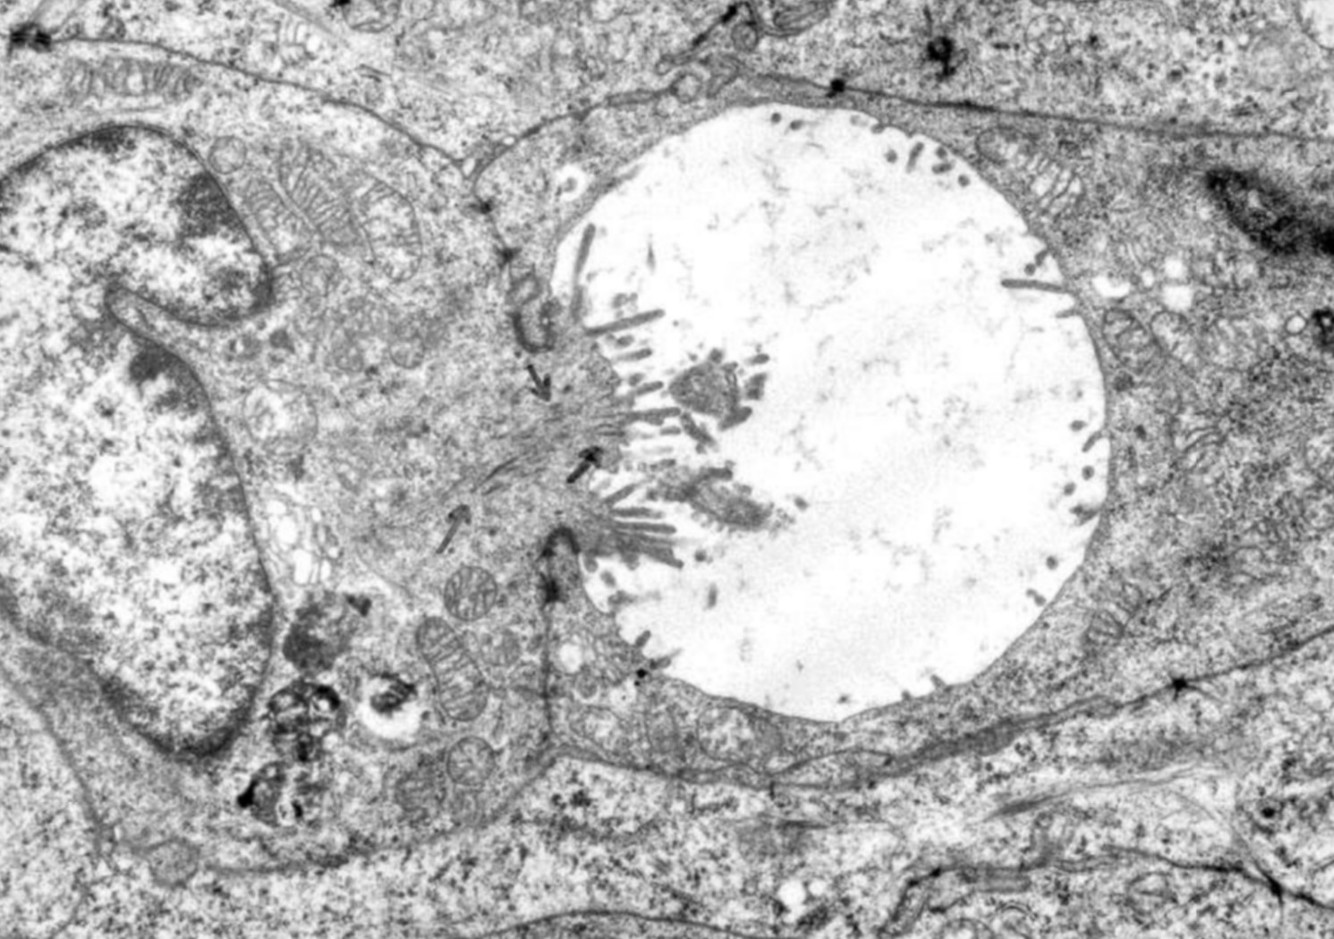

NEUROENDOCRINE NEOPLASMS

• NUMEROUS DENSE CORE GRANULES